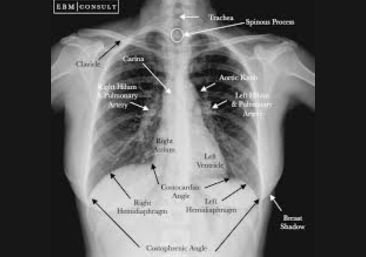

When it comes to diagnosing lung problems, sometimes imaging alone isn’t enough. That’s where a bronchoscopy becomes an essential tool.